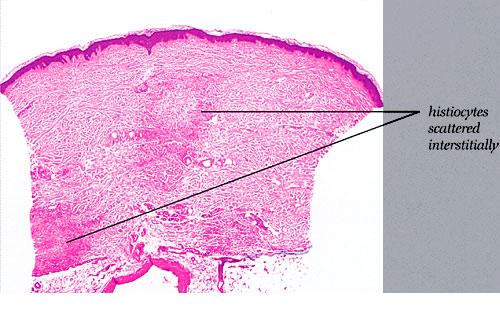

Read MoreInterstitial granuloma annulare = الورم الحبيبي الحلقي الخلالي Granuloma Annulare Granuloma annulare is a benign self-limited disease, first described by Colcott-Fox1 in 1895 and Radcliffe-Crocker in 1902. EPIDEMIOLOGY Granuloma annulare is a relatively common disorder. It occurs in all age groups but is rare in infancy. The localized annular and subcutaneous forms occur more frequently […]